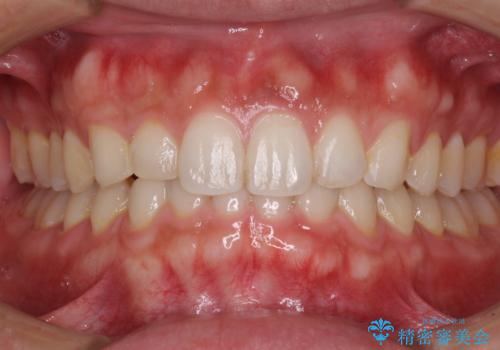

【モニター】インビザラインで口を閉じやすく

- 前に出ている上顎前歯が気になるとのことで来院された患者様です。

インビザラインを用い、IPR(歯と歯の間を削る)と歯列全体を後方に移動させることで、可能な限り前歯の突出感を改善することとしました。

元々の歯列も整っており、横顔の印象の出っ歯ではなかったため、仕上がりに満足できない可能性があると心配しておりましたが、口が閉じやすくなり、患者様には大変満足していただきました。